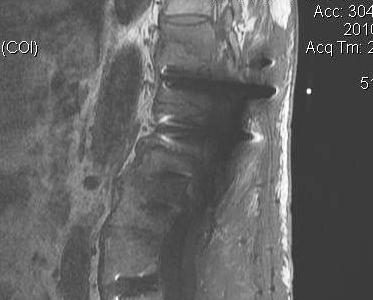

Surgical Indications

Failure non operative management

Epidural abscess

Deformity

Options

1. Percutaneous Discectomy and Drainage

Li et al Arch Orthop Trauma Surg 2011

- 31 patients with post-operative discitis

- half had positive cultures, other half sterile

2. Laminectomy and Drainage